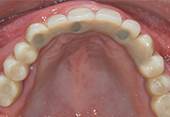

Ausgangslage: Der Patient wünscht sich nach Jahren der Zahnlosigkeit im Oberkiefer einen festsitzenden Zahnersatz. Der Knochenabbau ist noch -

Die mit einem speziellen Verfahren hergestellte Chirurgieschablone ermöglicht eine sehr atraumatische Chirurgie (ohne Aufklappung der -

Schlusssituation: Die gute Positionierung der Implantate ermöglichte die Herstellung einer verschraubten, festsitzenden